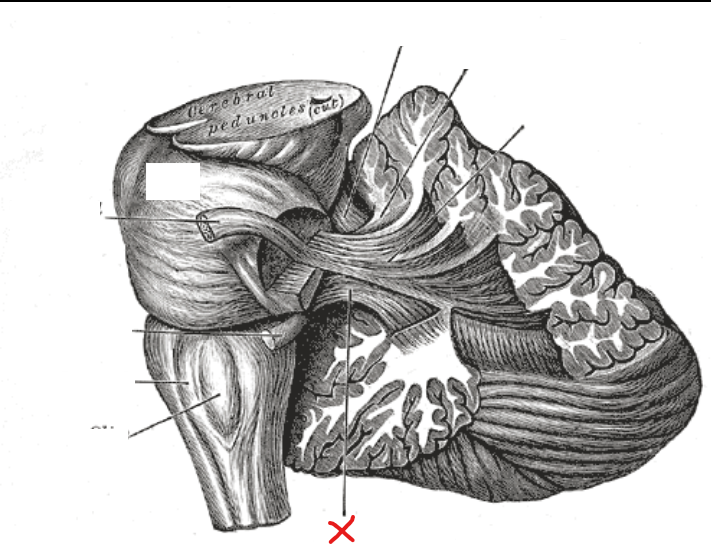

What is X

Fasciculus gracilis

Fasciculus cuneatus

What are the fasciculus gracilis and fasciculus cuneatus together called

Dorsal column

Are the dorsal columns ascending or descending tracts

Ascending tracts

Where do the ascending tracts begin in

Spinal cord

Where do the ascending tracts terminate in

Medulla in nucleus gracilis and nucleus cuneatus

5

Gracile tubercle

1

Cuneate tubercle

Posterior median sulcus